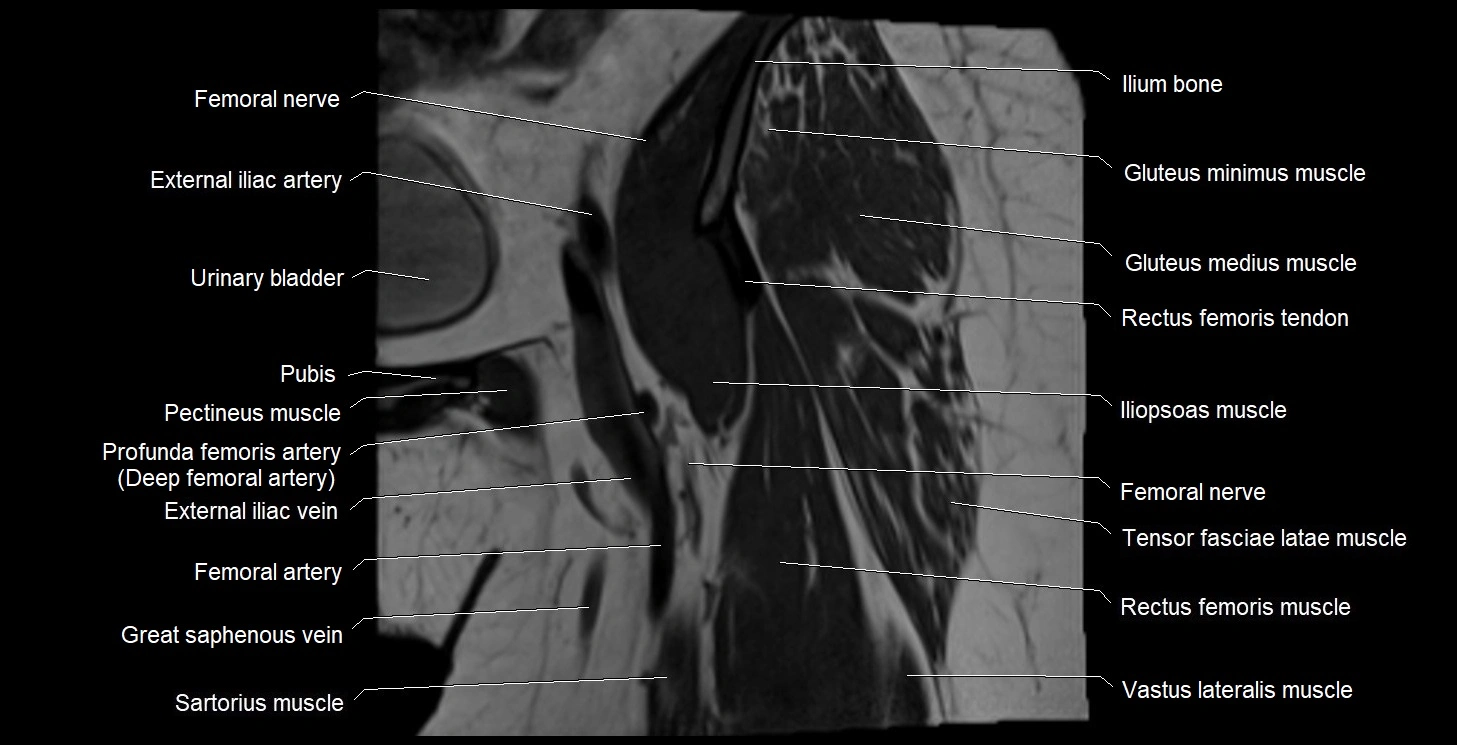

- External iliac artery

- External iliac vein

- Femoral nerve

- Gluteus medius muscle

- Gluteus minimus muscle

- Gracilis muscle

- Iliopsoas muscle

- Iliopsoas tendon

- Ilium bone

- Pectineus muscle

- Rectus femoris muscle

- Rectus femoris tendon (Proximal tendon of rectus femoris)

- Sartorius muscle

- Tensor fasciae latae muscle

- Urinary bladder

- Vastus lateralis muscle